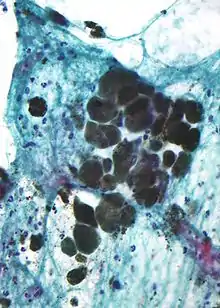

Micrograph of Melanin pigment (light refracting granular material—center of image) in a pigmented melanoma.

Melanin is brown, non-refractile, and finely granular with individual granules having a diameter of less than 800 nanometers. This differentiates melanin from common blood breakdown pigments, which are larger, chunky, and refractile, and range in color from green to yellow or red-brown. In heavily pigmented lesions, dense aggregates of melanin can obscure histologic detail. A dilute solution of potassium permanganate is an effective melanin bleach.[54]